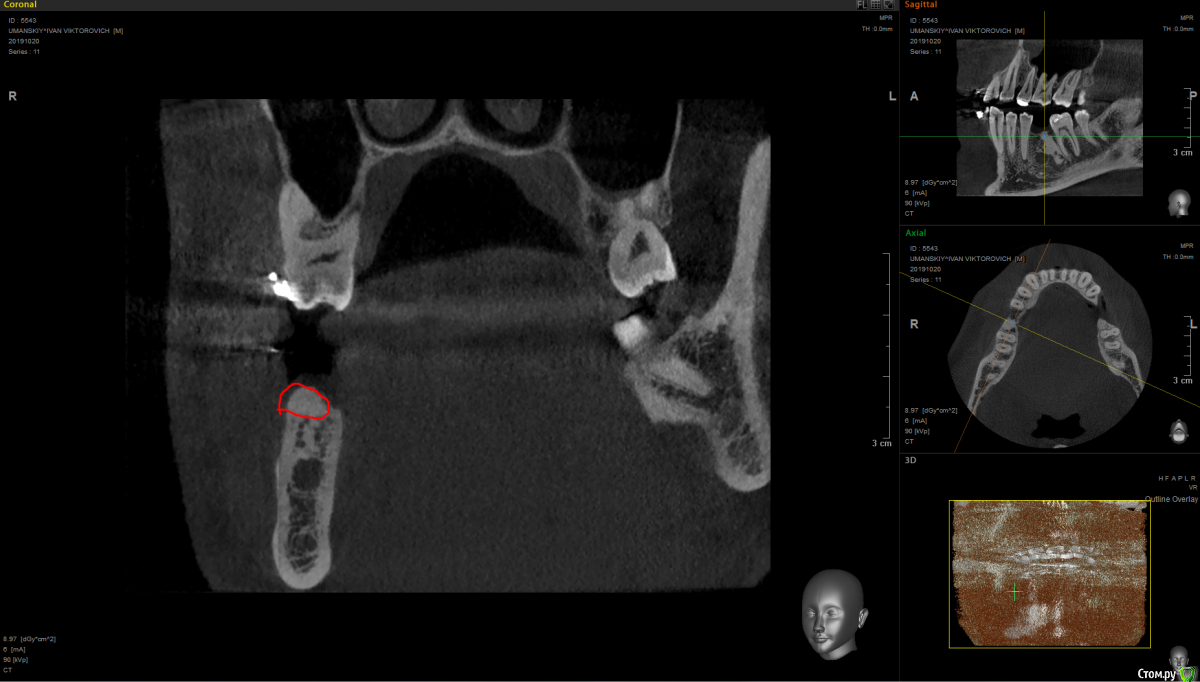

It'sGeorgy Опубликовано 15 января, 2020 Поделиться Опубликовано 15 января, 2020 Здравствуйте!На 2ом прикреплении явно следствие, на 3 и 4 - причина. Вижу 2 варианта развития событий:1: Разрезать, отслоиться. Посмотреть что явилось причиной, удалить причину. Начать готовить ложе под имплантат. 4.0 фрезой провалиться в полость кисты, попытаться извлечь ее через ложе. Поставить имплантат.2: Если через ложе извлечь не удастся, то пойти вестибулярным доступом. Извлечь. Графт, мембрана. 5 мес отдыха. Имплантат. Кто подобным уже занимался, подскажите, насколько перспективен первый вариант? Возможно ли по КТ понять что явилось причиной? На корень не особо похоже. Для остеомы тоже нетипичная картина. Ссылка на комментарий

shy Опубликовано 15 января, 2020 Поделиться Опубликовано 15 января, 2020 (изменено) резидуальная пошел бы через вестибулярный доступ , с графтом или без на усмотрение оперирующего . P.S причину уже удалили до Вас Изменено 15 января, 2020 пользователем shy 1 Ссылка на комментарий

It'sGeorgy Опубликовано 7 февраля, 2020 Автор Поделиться Опубликовано 7 февраля, 2020 (изменено) Заколхозил лоскут => налепил житкотекучего на кость(стрелкой на снимке), чтобы понять там ли планирую пилить, сделал оптг => выпилил => вытащил => через месяц пластика мягких тканей + имплантат. А ментальное отверстие в 2 мм от окна отлично держало меня в тонусе на протяжении все операции. Изменено 7 февраля, 2020 пользователем It'sGeorgy 1 Ссылка на комментарий

Spon Опубликовано 8 февраля, 2020 Поделиться Опубликовано 8 февраля, 2020 Заколхозил лоскут => налепил житкотекучего на кость(стрелкой на снимке), чтобы понять там ли планирую пилить, сделал оптг => выпилил => вытащил => через месяц пластика мягких тканей + имплантат. А ментальное отверстие в 2 мм от окна отлично держало меня в тонусе на протяжении все операции.Все правильноПытаться удалить образование через 4 мм отверстие это заведомо провальная тактика,не получилось бы,маленькое окноКиста рецидивирует если оставить хоть немного оболочки,надо вычищать полностью до гладкой кости Ссылка на комментарий